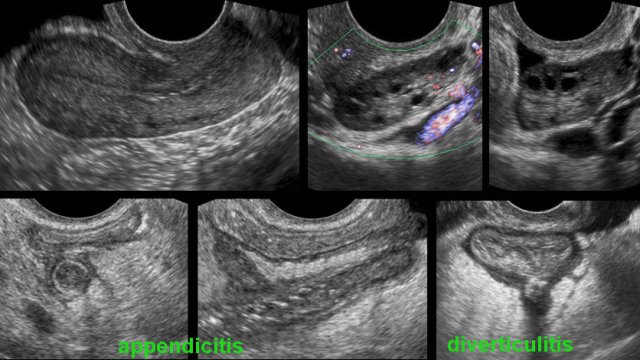

Transvaginal ultrasound (TVUS) has great advantages in visualizing the uterus and ovaries.

It can also be used for non-gynaecological conditions such as appendicitis, diverticulitis, etc.

The use of transvaginal ultrasound will be dealt with in a different article: TVUS for non-gynaecological conditions.